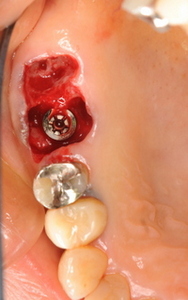

次の2症例は抜歯即時埋入インプラントです。

歯ぐきは切開していないことがご理解していただけると思います。

抜歯窩にインプラントを埋入しますので、

まわりの歯ぐきを通常のインプラントのように切開する必要が

ありませんで、インプラント手術後の痛みや腫れも少ないという

利点があります。